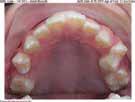

LOVE YOUR SMILE!

Mahaffey Linkous Orthodontics offers braces and lnvisalign® in conjunction with modern techniques to conveniently uncover your best smile. Dr. Michael Mahaffey, Dr. Eric Linkous, and their caring team of tooth-moving experts make having orthodontic treatment an awesome experience! Schedule your complimentary consultation today to begin your journey to a healthier, more confident smile.

Mahaffey Linkous Orthodontics

770-487-6439

www.peachtreecitybraces.com